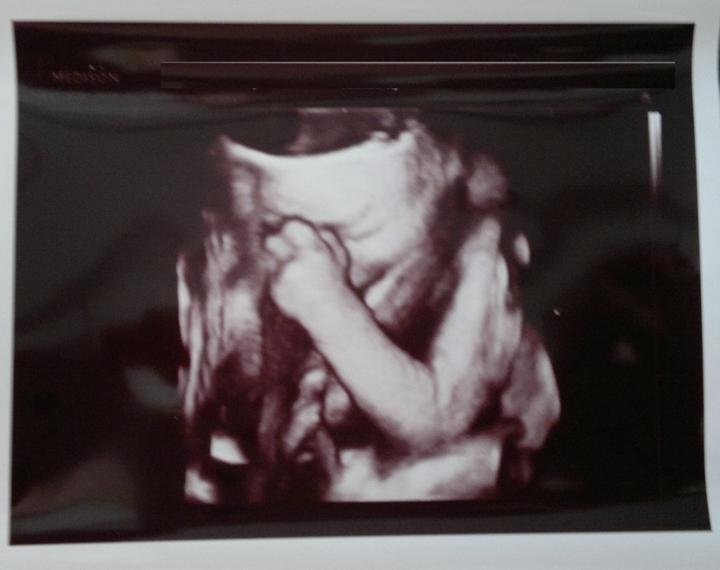

Jáchym Pavel Kolařík - 2. těhotenství

Termín porodu dle PM - 29. 8. 2014

( porod byl skutečně 24. 8. 2014 )

VIKTORIE / JÁCHYM